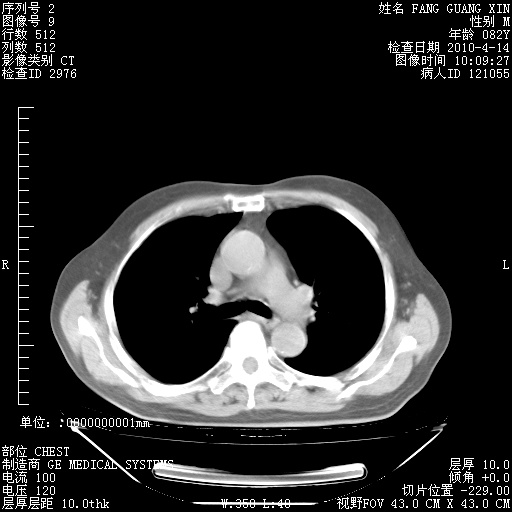

4月14日肺部CT

27.JPG

28.JPG

29.JPG

30.JPG